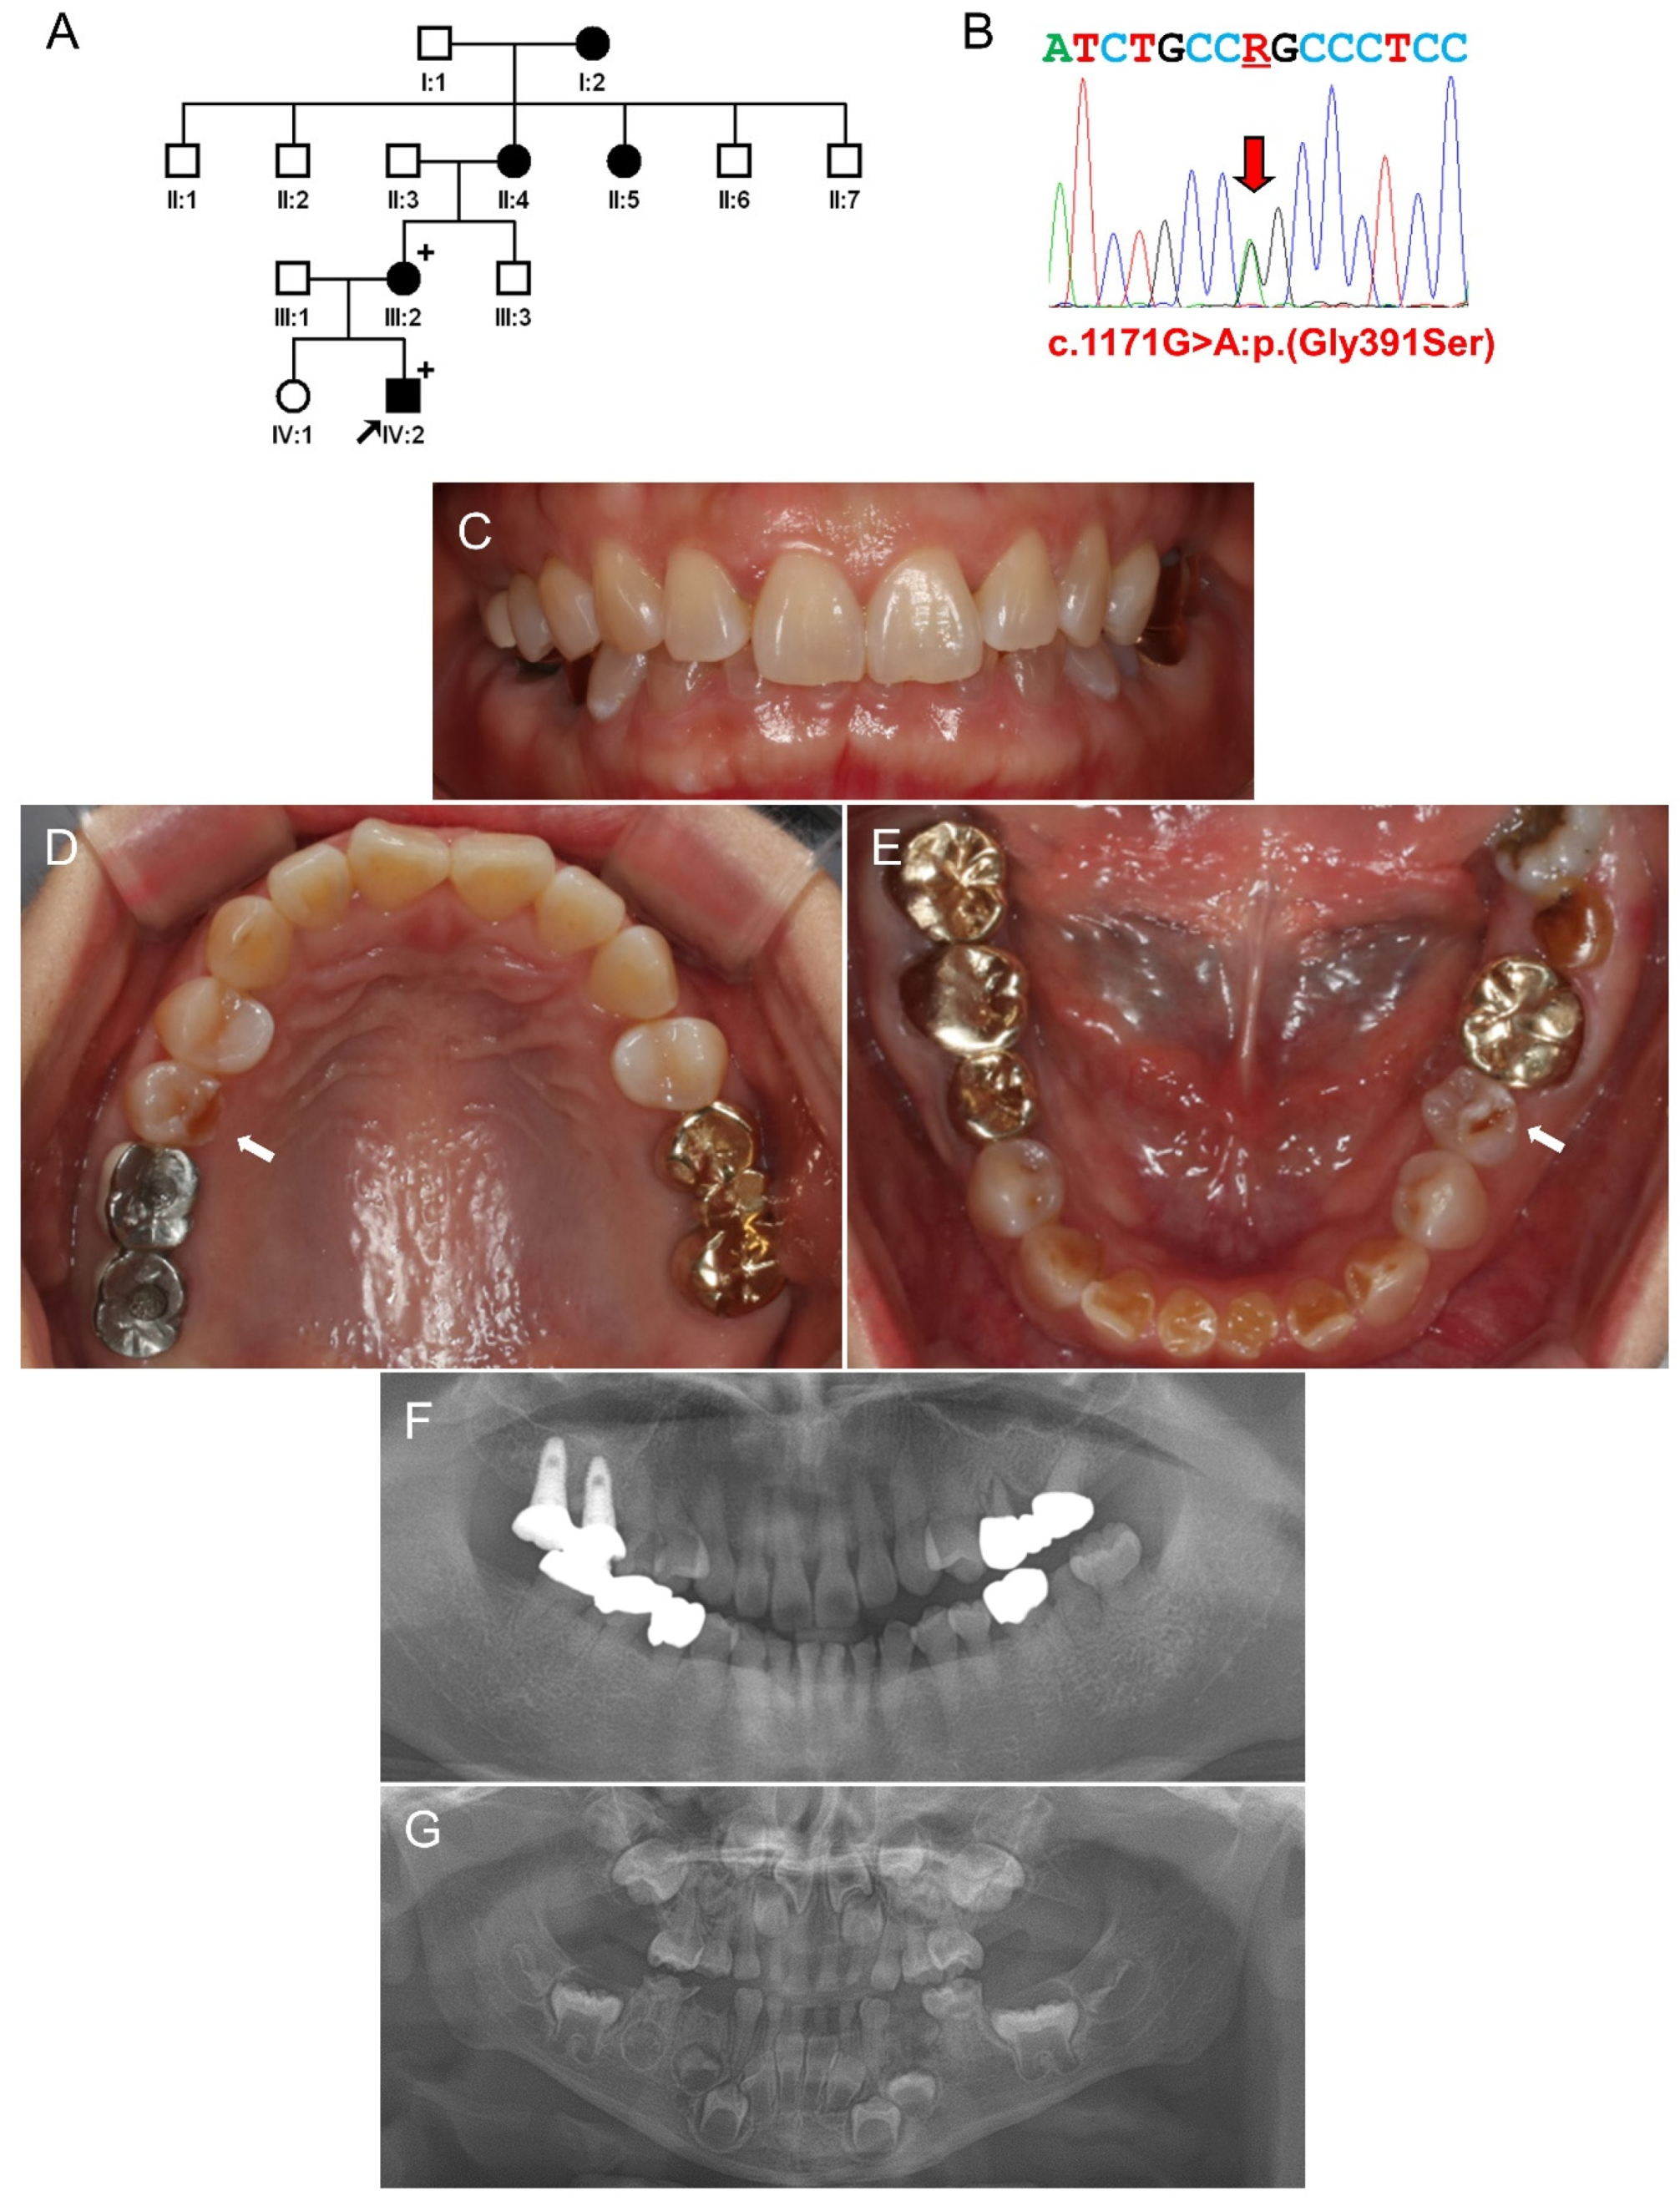

3.2. Family 2